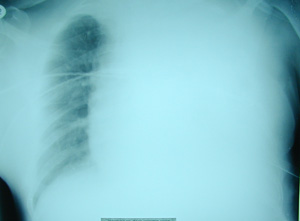

Εικόνα 3

Οπισθιοπροσθία ακτινογραφία του θώρακος μετά από την αποτυχή εκκένωση του αιμοθώρακος με την τοποθέτηση του σωλήνα παροχέτευσης. Παρατηρείται εκ νέου συλλογή αίματος και μετατόπιση του μεσοθωρακίου, προς την υγιή πλευρά.